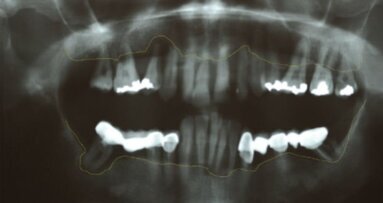

Una paziente di 69 anni si è presentata nel nostro studio. Tranne i denti 17 e 27, la mascella era edentula. I restanti denti non potevano essere conservati a causa della situazione parodontale. Una protesi provvisoria rimovibile è stata ancorata ai molari superiori. La paziente ha richiesto una protesi fissa per ripristinare definitivamente la funzione masticatoria e l’estetica. L’esame clinico e radiografico ha dimostrato che l’osso era sufficiente per posizionare gli impianti che avrebbero potuto sostenere una protesi fissa (Figg. 1 e 2), ed è stata progettata una protesi immediata con barra di ritenzione su sei impianti OsseoSpeed EV.